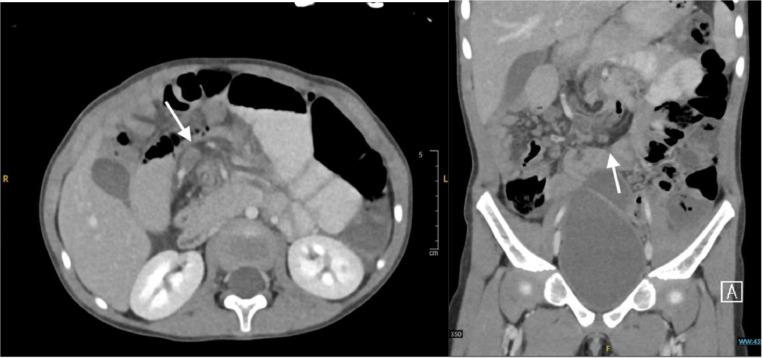

Midgut malrotations are rarely diagnosed beyond infancy. Delays in recognition and diagnosis can result in death. Here, we report the case of a 5-year-old girl who presented with a 1-year history of intermittent abdominal pain and vomiting. An abdominal computed tomography scan with contrast confirmed the diagnosis of midgut malrotation with obstruction; therefore, the Ladd procedure was performed, and the child was discharged uneventfully. Clinicians must maintain a high level of suspicion because this diagnosis is unusual in this age group.

中肠旋转不良在婴儿期之后很少被诊断出来。识别和诊断的延迟可能导致死亡。在此,我们报告一例5岁女孩的病例,她有1年间歇性腹痛和呕吐的病史。腹部增强计算机断层扫描确诊为中肠旋转不良伴梗阻;因此,实施了Ladd手术,患儿顺利出院。临床医生必须保持高度怀疑,因为这个年龄段出现这种诊断并不常见。